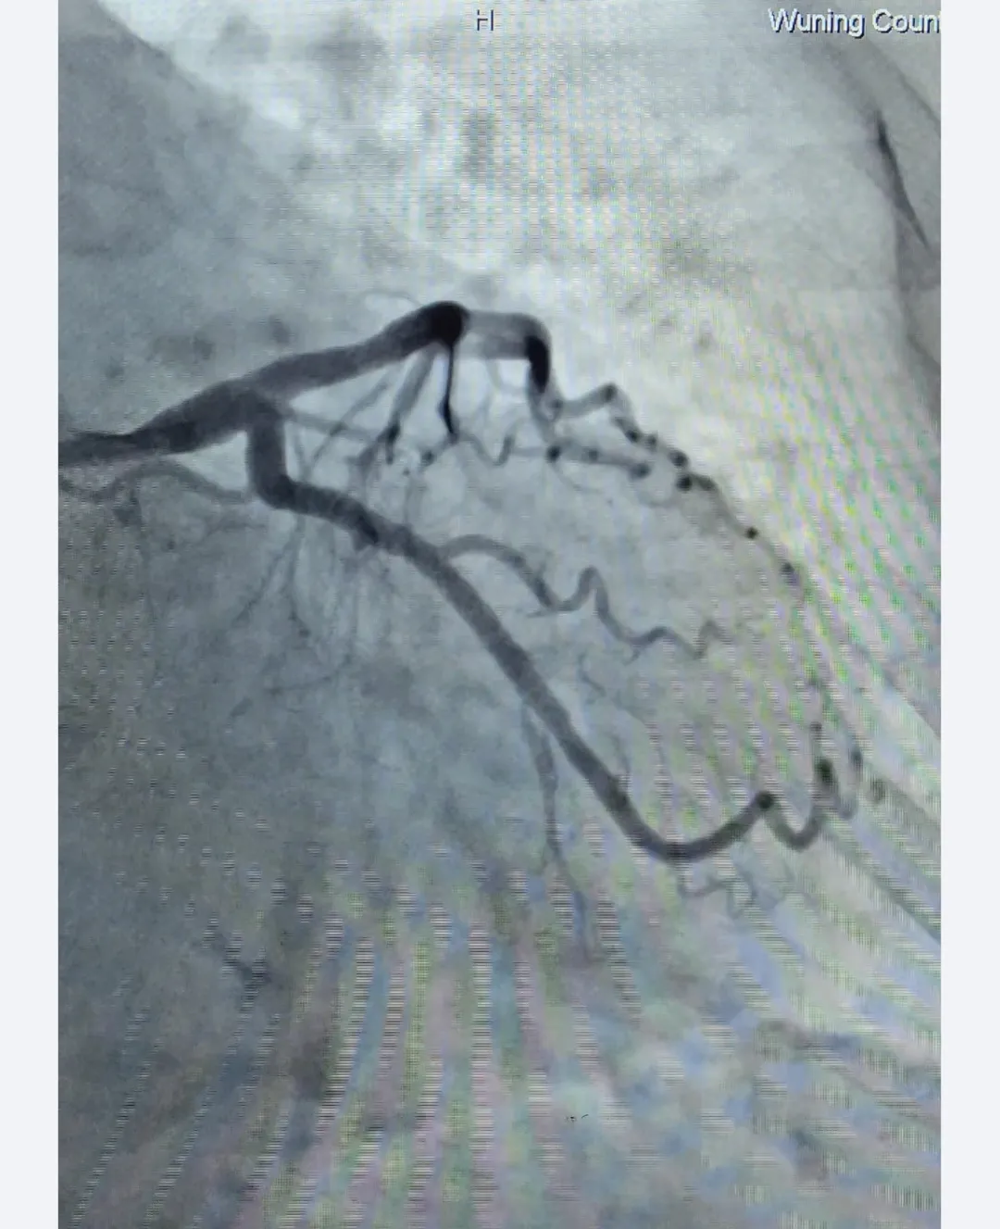

支架植入后